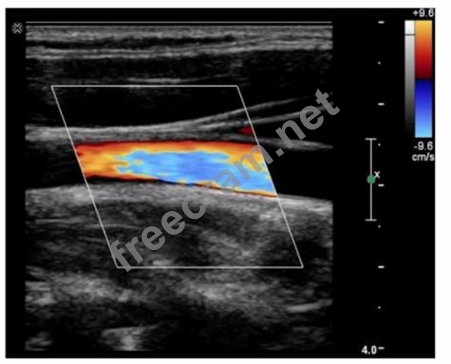

Which color Doppler artifact is visualized in this image?

Question 33: Which color Doppler artifact is visualized in this image? (E...